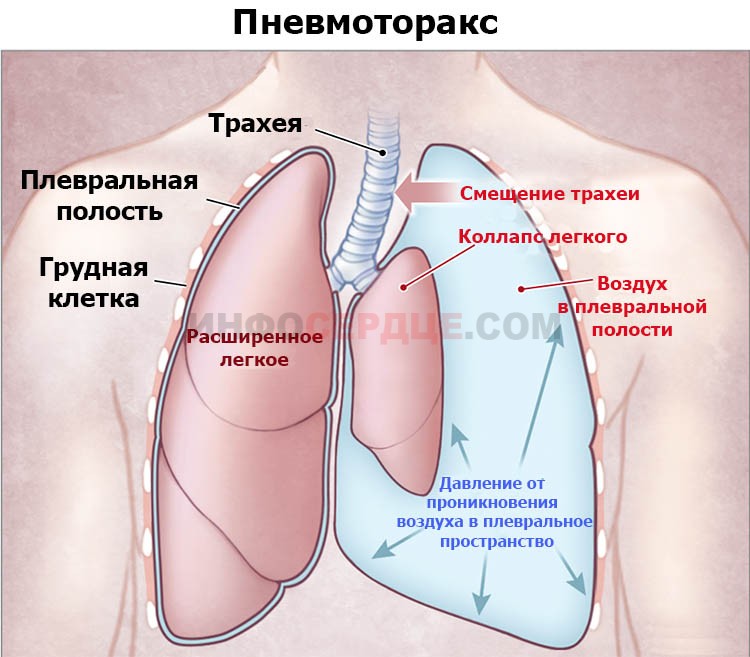

Схемы дыхания: Пневмоторакс на изображениях